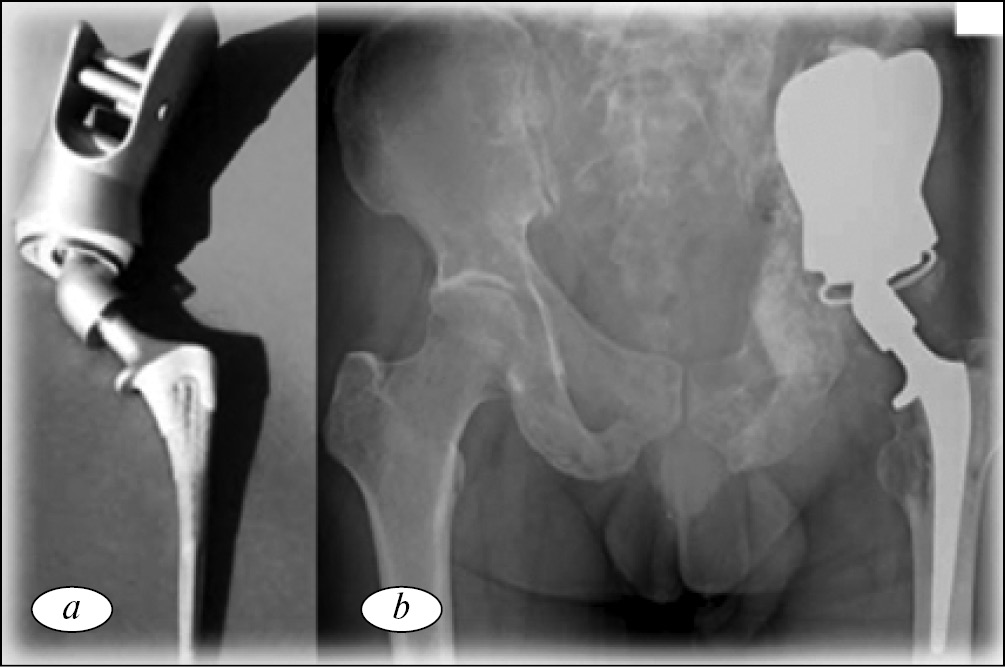

В клинике университета Южной Калифорнии (США) в период с 2000 по 2009 г. 25 пациентам с опухолевым поражением параацетабулярной области имплантированы модифицированные «седловидные» эндопротезы (рис. 5) [33]. Средний период наблюдения составил 29 мес. За время наблюдения прогрессирование заболевания выявлено у 15 (60 %) больных.

Рис. 5. Периацетабулярная реконструкция с применением «седловидного» эндопротеза: а — внешний вид; b — рентгенограмма костей таза, после выполненной операции. Металлоимплант фиксирован к резецированному крылу подвздошной кости [33]

Общее количество значимых осложнений — 11 (44 %). Глубокое инфицирование раны — у 6 (24 %), вывих протеза — у 3 (12 %) и перелом подвздошной кости с транспозицией эндопротеза — у 2 (8 %) пациентов. Среднее значение функционального результата по шкале MSTS составило 67 %.